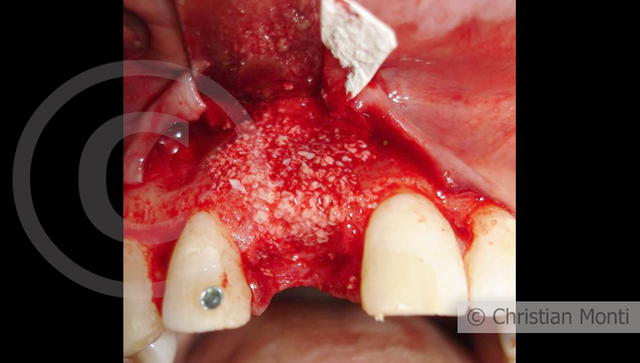

EDENTULIA SINGOLA

Impianto in sostituzione di un incisivo superiore